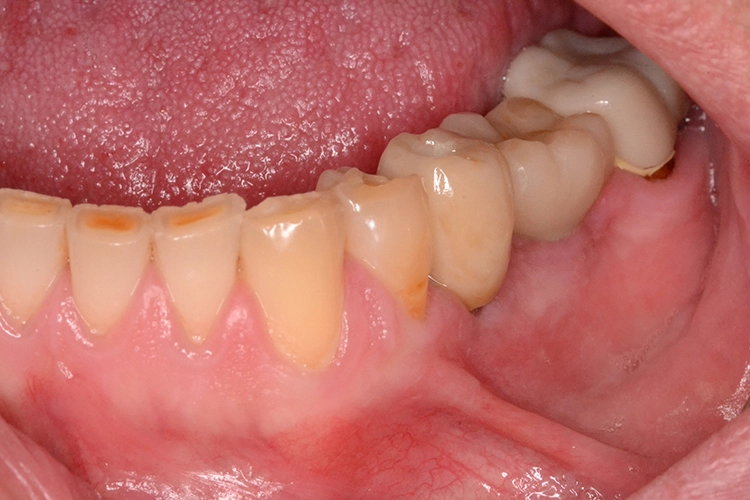

Aufgrund der Augmentation erfolgte die Freilegung 5 Monate postoperativ. Nach Ausformung des Emergenzprofils (Abb. 4i) erfolgte die definitive prothetische Versorgung durch eine okklusal verschraubte Einzelkrone (Abb. 4j).